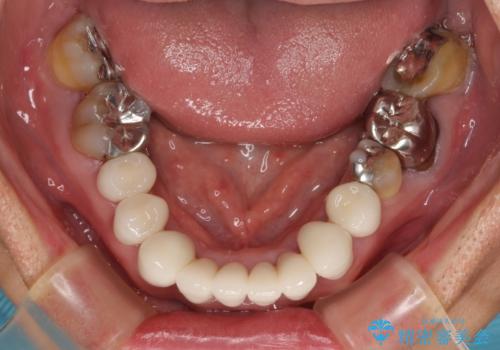

上下ともに前歯のセラミッククラウンによる補綴治療を希望されていましたが、下顎前歯は叢生が強いため、補綴治療前に部分矯正を行って歯列を整えた上で、補綴治療を行うこととしました。